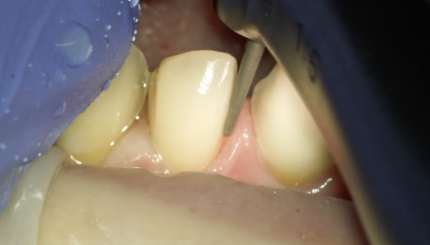

43 42 41 31 32 Финишное препарирование + ретракция

10 августа 2021